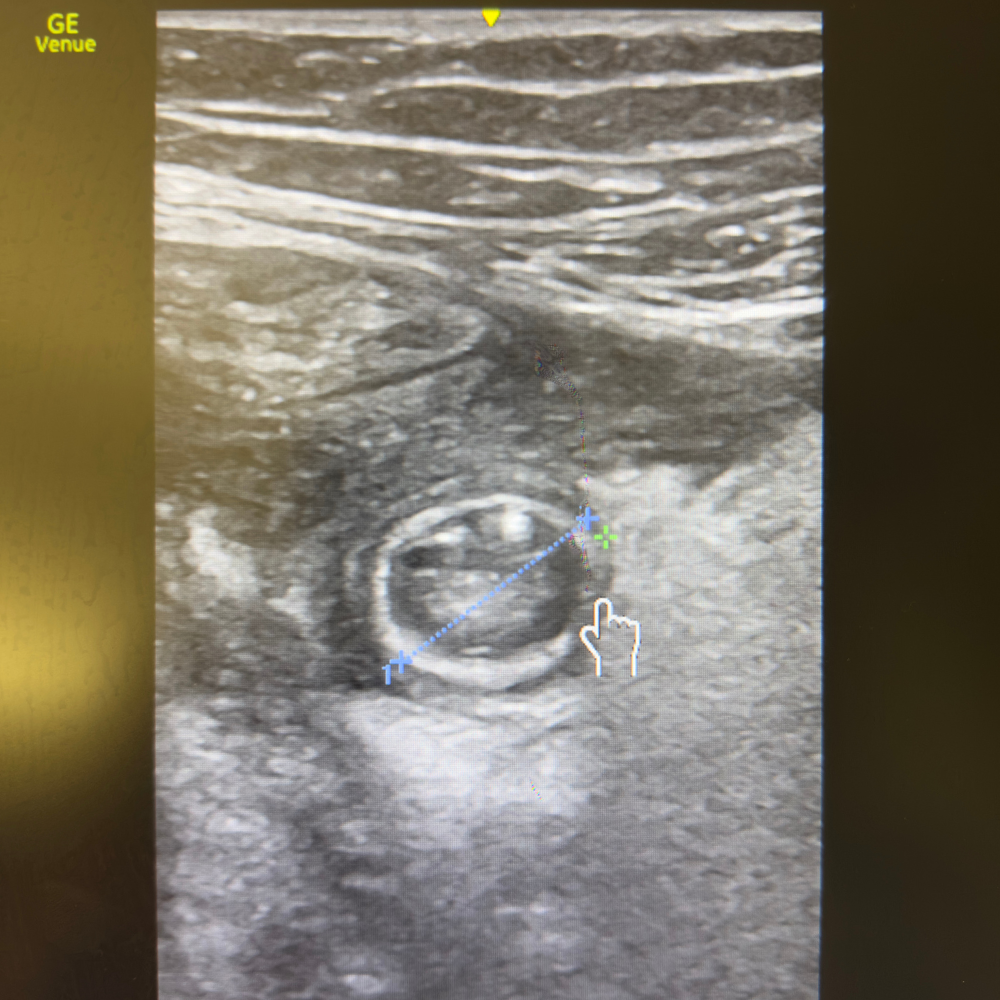

🔬 Aspect typique en coupe transversale

Image en cible (“target sign”)

Anneau hypoéchogène périphérique

Centre plus échogène

Absence de péristaltisme

🩺 Critères d’Appendicite

- Appendice non compressible, en « cible », diamètre > 6 mm.

- Épaississement pariétal et hypervascularisation Doppler.

- Stercolithe échogène parfois visible avec cône d’ombre.

- Graisse péri-appendiculaire hyperéchogène (inflammation).

- Collection anéchogène = abcès ou perforation.